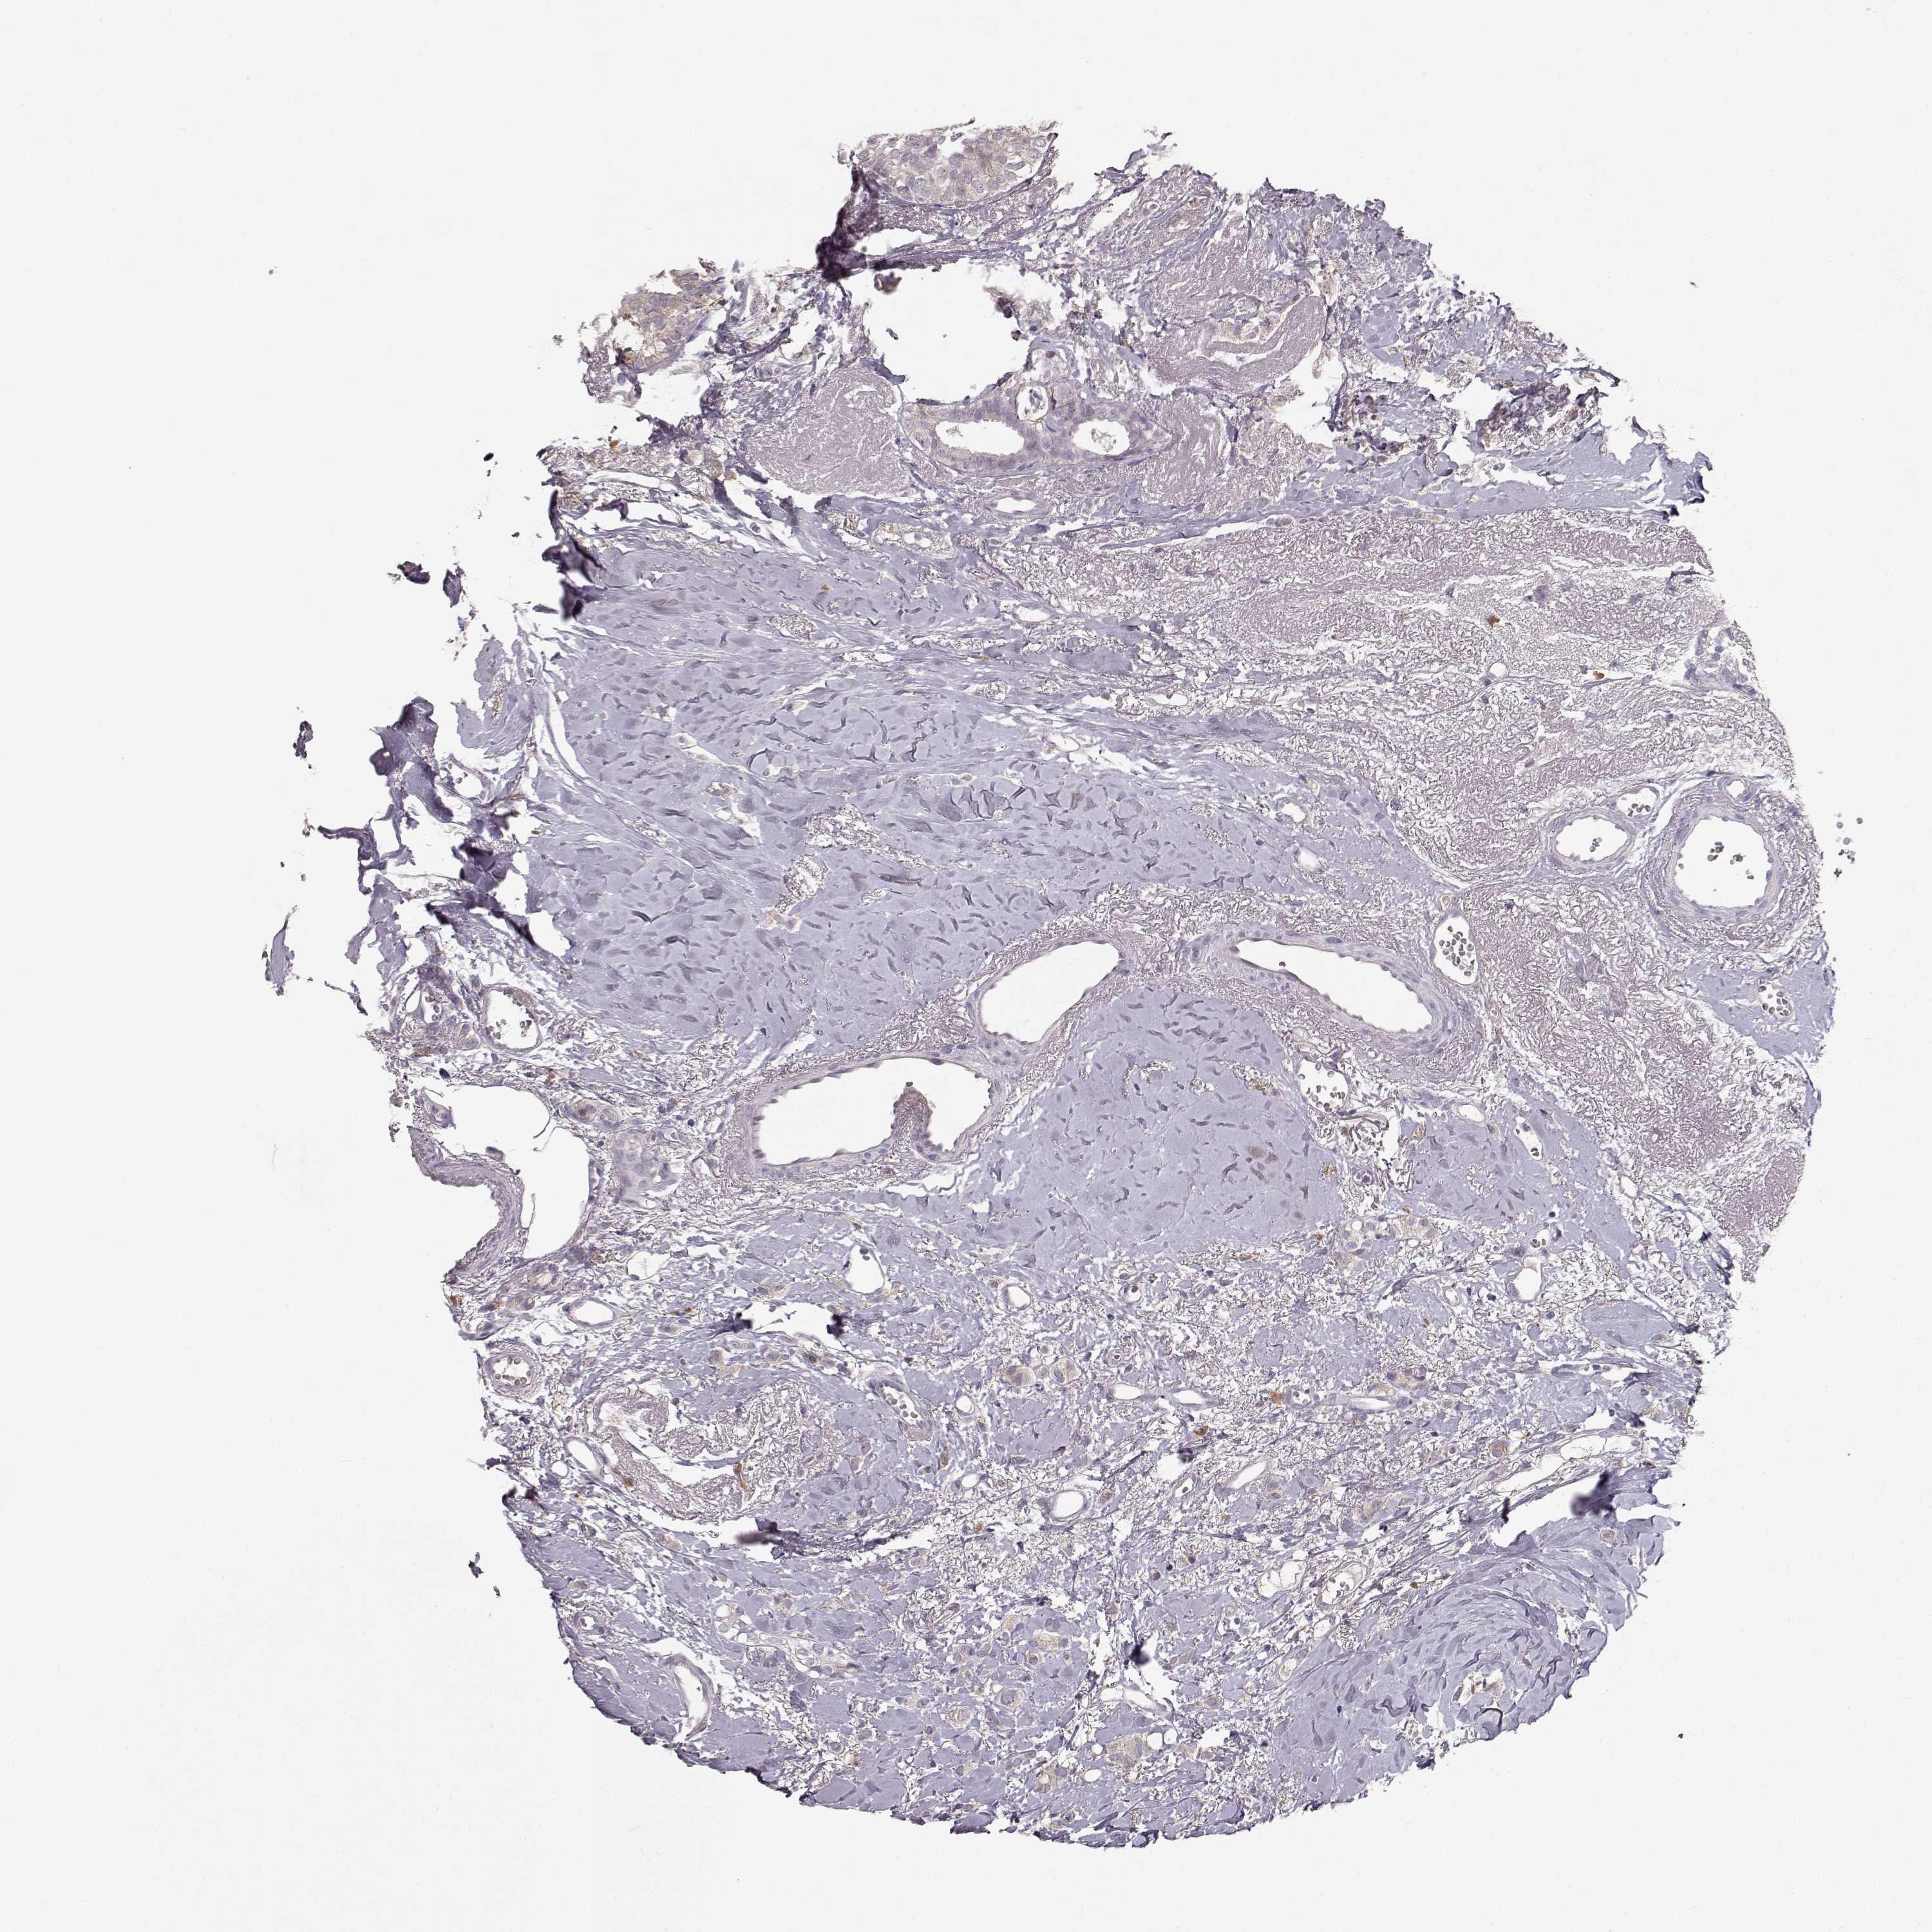

CANCER BREAST CANCER Show tissue menu

BRCA TCGA BRCA VALIDATION PROTEIN EXPRESSION